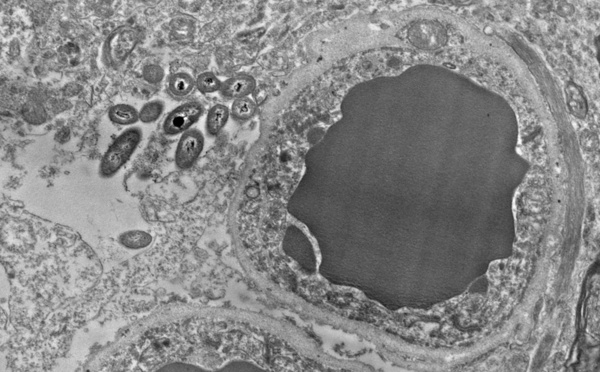

El cerebro podría tener su propia microbiota - 15/11/2018

Científicos norteamericanos han descubierto bacterias intestinales en el cerebro humano que aparentemente desempeñan las mismas funciones inmunológicas. Tal vez configuren también nuestra identidad, al igual que la microbiota intestinal.